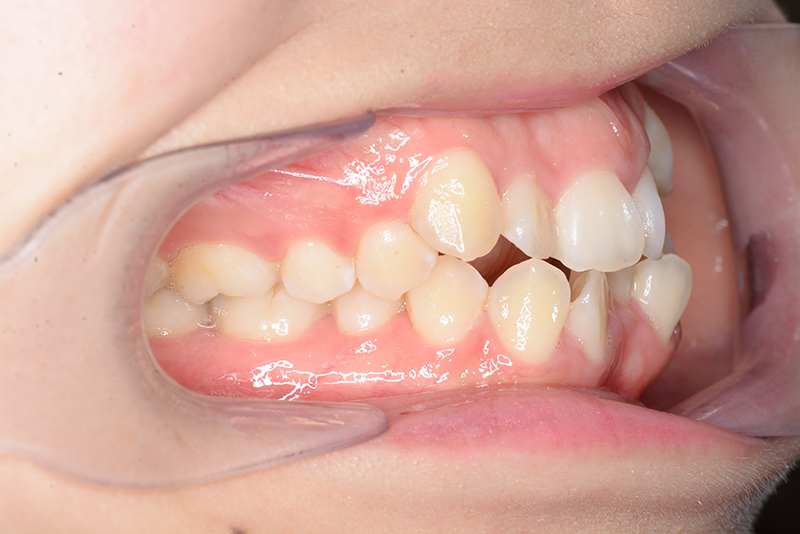

| 口腔内所見 | over jet 4.5mm、over bite 4.0mm、大臼歯関係 I級で上下顎前歯部に叢生が認められた。 |